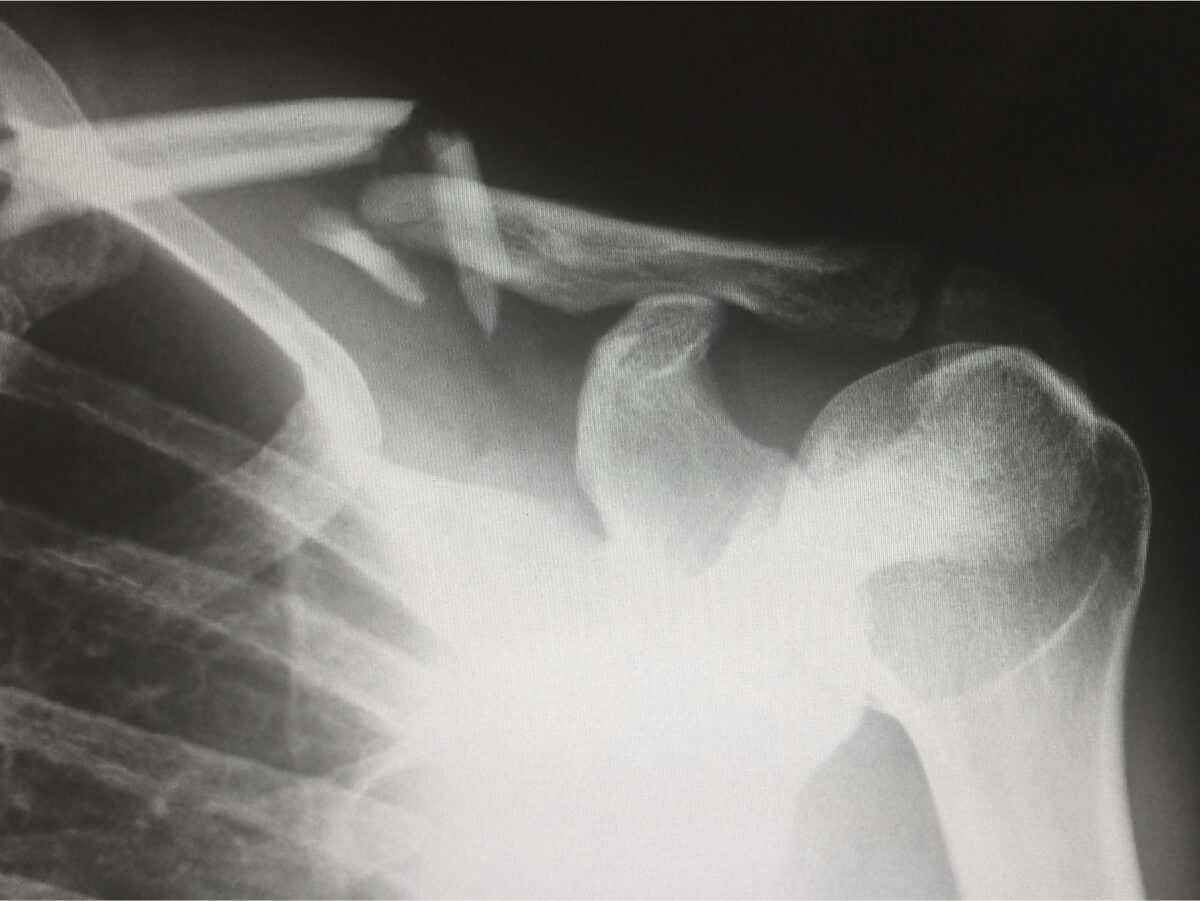

Un cartilage atteint va s’user précocement, lentement mais régulièrement. La fonction de ce tissu étant d’amortir les chocs entre les os, des frottements apparaîtront alors et lors des crises, les mouvements pourront devenir douloureux. Les os, ainsi anormalement sollicités, pourront alors créer des excroissances osseuses, les ostéophytes. La réalisation d’une radiographie permet d’évaluer les atteintes et l’évolution de la pathologie.